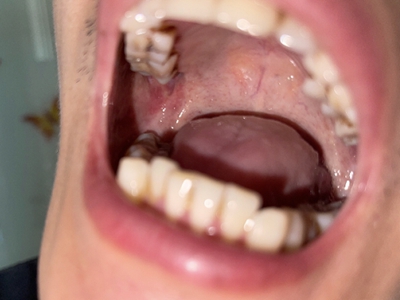

舌头

溃疡

溃疡性口炎舌头下有凸起的溃疡图

溃疡性口炎舌头下面舌系带两边明显充血、水肿,其上有多个大小不一的溃疡面,附有黄白色假膜,质地较厚,略突出于黏膜表面,散在分布,部分相互融合。